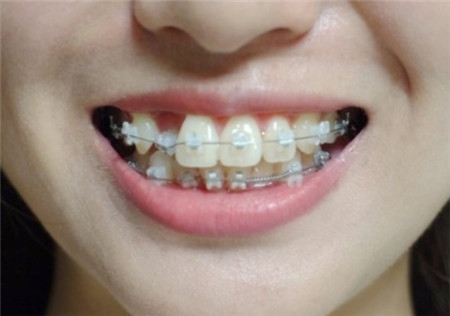

现在可以看到上下牙齿正中线对齐呈一字型。其实以前比有虎牙更让我郁闷的是上下牙齿的正中线不对齐,矫正后现在已经完美。

原以为矫正器摘掉之后就结束了,先让我哭会儿……牙齿内侧还有小白齿部位要贴小细铁丝,还有整体套在牙上的透明保持器,还要再戴两年,还真是没完没了的矫正…… 戴橡皮筋和透明保持器的两年间,除了吃东西的时候摘掉以外要一直带着,有一种重新开始矫正的感觉。

下面是我的牙齿矫正中不同阶段的变化: